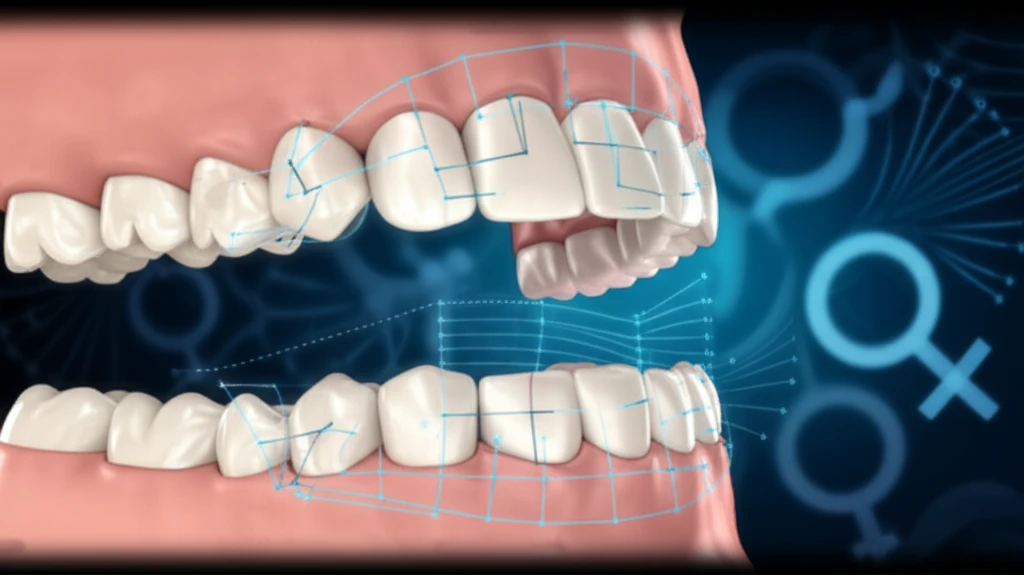

Bite marks, defined as impressions made by teeth alone or in combination with other mouth parts, are a unique form of dental evidence. Forensic odontologists analyze these marks, examining their shape, size, and position to match them with a suspect's dentition. This process can reveal individual tooth marks, double-arched patterns, or even multiple overlying bruises, each providing critical information. However, bite marks can be altered by factors like skin elasticity, pressure applied during the bite, and the angle of the jaw, making accurate analysis challenging.

Recognizing these challenges, a team of researchers introduced a novel approach to bite mark analysis using computer-assisted methods. Their study aimed to evaluate bite marks in both males and females using an indirect, computer-assisted technique focusing on intercanine distance (ICD) and other angular measurements. The goal was to determine if this method could reliably differentiate between genders, thereby enhancing the accuracy and efficiency of forensic investigations.

- Measurements: The software was used to measure several parameters: Intercanine distance (ICD), defined as the perpendicular distance between the mid-point of the central incisors to the intercanine line (line AB); Angles ABX and ABY, formed by lines drawn from the distal aspect of the central incisors to the midpoint of line AB.